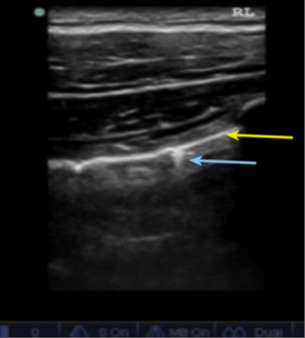

During inspiration and expiration, the visceral pleura back and forth adjacent to the parietal pleural '' moves'' which is known as pulmonary sliding. The hyperechoic bright line represents the junction of the visceral pleural with the parietal pleura, which adheres to the lung as it moves and slides during normal inspiration and expiration, is seen on real-time ultrasound and is a normal finding (Figure 8). The absence of the sliding lung is a direct sign of pneumothorax, but not conclusive, the cardinal sign being the lung point that represents the transition between viable lung and pneumothorax.

To complete the E–FAST exam, the chest is scanned anteriorly and bilaterally to exclude the presence of pneumothorax and hemothorax. Depending on the patient's body habitus, better resolution is obtained for this evaluation using a high-frequency, shallow-depth linear transducer (10 MHz linear probe) in the case of pneumothorax; and the convex or sector transducer (which have a lower frequency between 3-5 MHz and greater depth) to track hemothorax.

Placement of the linear transducer in the region of the anterior thorax between the 2nd and 3rd intercostal space in the midclavicular line (pneumothorax evaluation).

Both lungs are evaluated for the presence of lung sliding (lung sliding) whose presence rules out the presence of pneumothorax.6 To confirm the diagnosis of pneumothorax by moving the probe both inferiorly and laterally with the notch directed towards the head, looking for the pulmonary point sign that is pathognomonic of pneumothorax, which represents the transition point between the pulmonary parenchyma and air in the pleural cavity (pneumothorax), is seen depicted in B-mode; alternating pulmonary slippage with its absence; and in M mode interspersed as beach and stratosphere signs.

Also in M-mode, look for the beach sign (absent in pneumothorax) and the stratosphere sign found in pneumothorax.

US signs in pneumothorax: absence of pulmonary sliding, pulmonary dot sign, stratosphere sign, or barcode.

US signs that rule out pneumothorax: presence of B lines, presence of pulmonary sliding, beach sign.

In B-mode; Presence of normal lung slip (lung sliding); Yellow arrow pleural movement (visceral and parietal) and in blue date vertical lines in comet tails.

In M-mode; Sign of the Beach Blue arrow the waves of the sea: Corresponds to soft parts and in yellow the sand: corresponds to normal lung tissue.